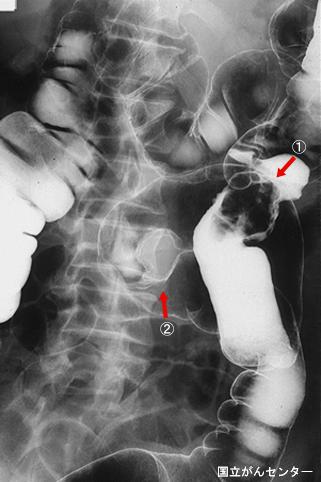

질환(병리주체)의 분류 전이성종양/

부위(장기별) 대장/2구역 이상의 대장에 걸치는 것

검사방법 X-P

종양의 최대경(밀리미터) 40이상

다발종양(동일 장기) 유(동시성)

다중종양(다수의 장기) 유(이시성)